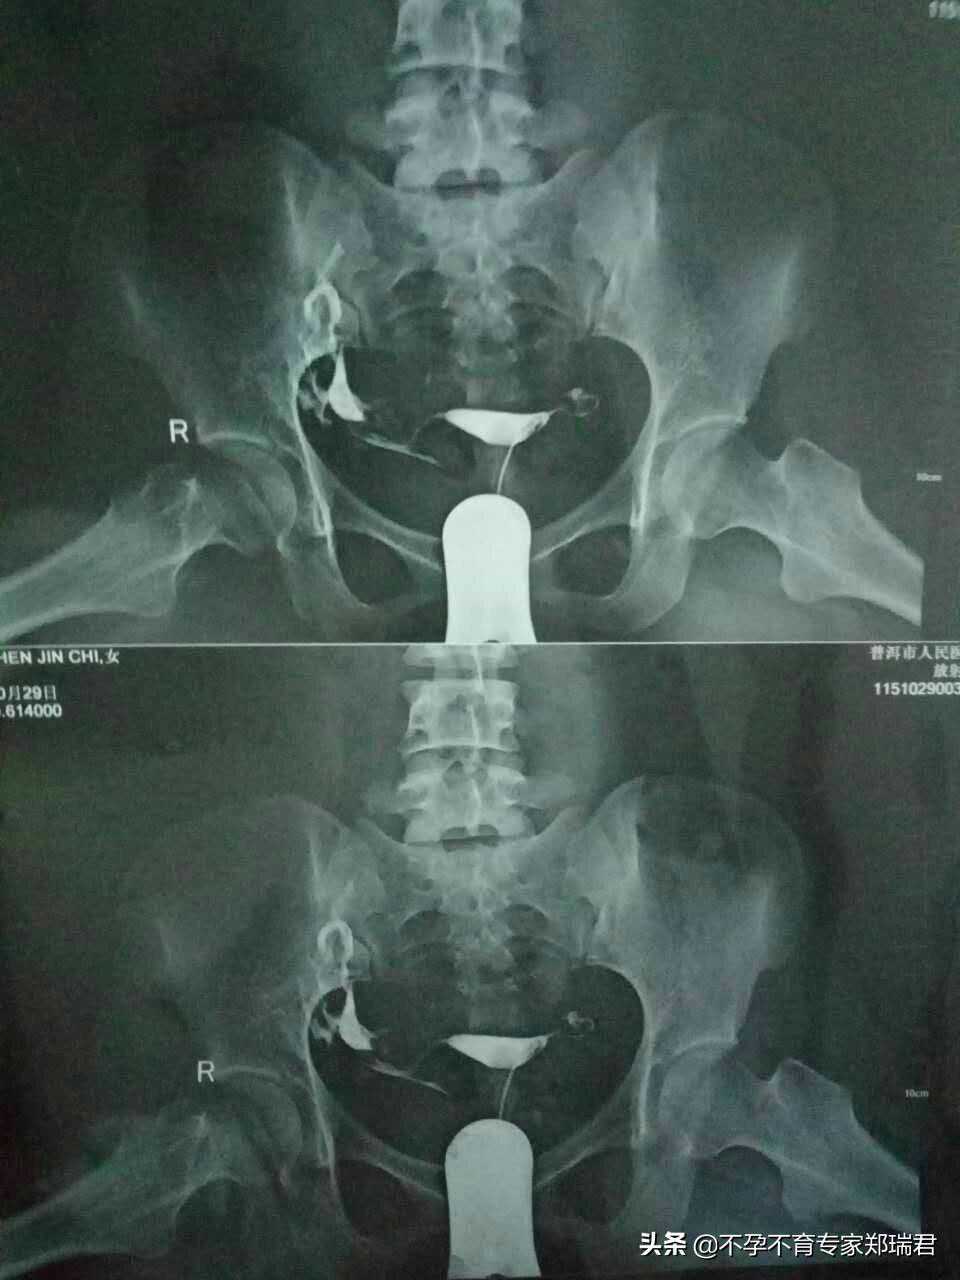

诊治经过❖陈女士36岁(中国籍),丈夫AKIYA~37岁(日...